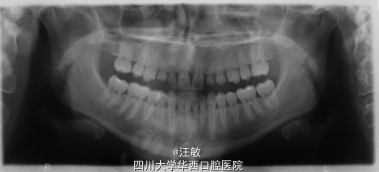

患者女性,要求改善上前牙形态。自诉上颌侧切牙和尖牙没换过牙。

检查发现上中切牙间隙较大,上颌乳侧切牙和乳尖牙滞留。双侧前磨牙有轻度扭转。高位笑线。牙周组织有炎症,探诊出血,无牙周袋。 全景片发现上颌第二磨牙缺失,乳侧切牙和乳尖牙牙根较短,有吸收,无恒牙胚。

诊断模型进行分析,上中切牙间隙约2mm,左侧乳侧切牙和乳尖牙修复空间为17mm,右侧为15mm。基于患者乳牙有牙根吸收,建议拔除所有滞留乳牙,其后进行种植修复。上切牙冠修复。面弓转移记录颌位关系。